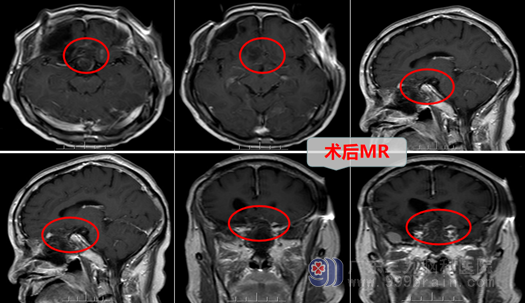

欧阳教授热情接待了他,将他收在神经外十科住院,完善术前检查后,欧阳教授带领医疗团队讨论,决定先在内镜下扩大经鼻蝶入路行鞍结节、左侧前床突及左侧前颅窝底多发脑膜瘤切除术。术中扩大磨除鞍底及左侧部分额底,可见肿瘤突入鞍上挤压视交叉及双侧视神经,左侧视神经受压明显,垂体柄左侧偏移,顺利剥除鞍区肿瘤,左侧前床突处及左侧额底可见肿瘤组织,一并切除。

术程顺利,陈叔行微创手术切除脑瘤,保住了左眼的视力,也减轻了术后许多不良反应。陈叔觉得这次手术比九年前开颅手术,反应轻多了,而且没有增加头部手术疤痕,所以陈叔高兴的说,专病还得专科治,找对医院及医生,是对自己最好的交代。